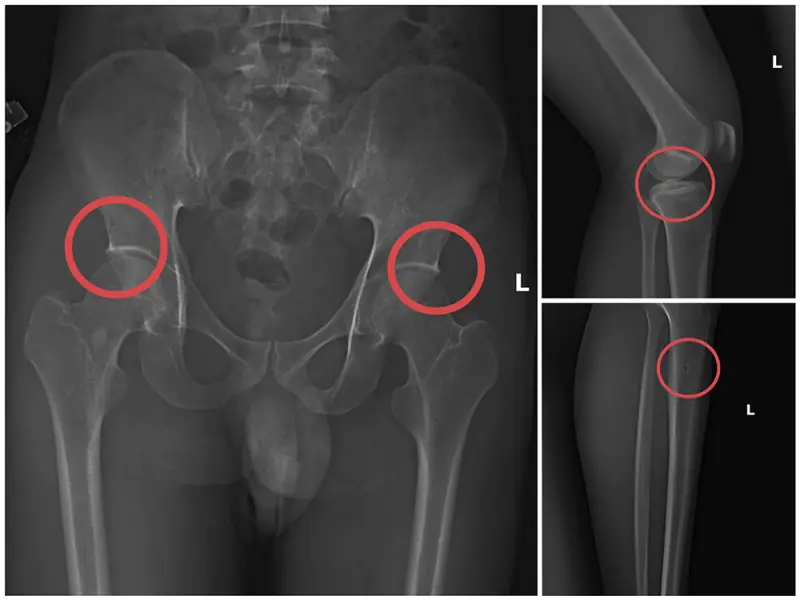

Tại đây, đối tượng Châu tiêm thuốc mê vào tĩnh mạch tay phải của người mua bảo hiểm, sau khoảng một phút họ bị mê đi thì Châu sẽ dùng búa và kim tiêm đục, đâm vào vùng cơ thể đã thống nhất từ trước để tạo vết tổn thương trên xương cho nứt, vỡ (thường sẽ làm rạn nứt, vỡ vùng xương chậu, xương đùi…).

Tiếp đó, đối tượng Châu đợi khoảng 10-20 phút khi thuốc mê hết tác dụng, những bệnh nhân tỉnh lại, anh ta hướng dẫn những người này tạo ra những vụ tai nạn tự nhiên để được hưởng bảo hiểm như: Bị điện giật ngã làm nạn nhân gãy xương chậu, đi suối ngã gãy chân... rồi nhờ người đưa đến Trung tâm y tế, bệnh viện khám và điều trị lấy bệnh án.